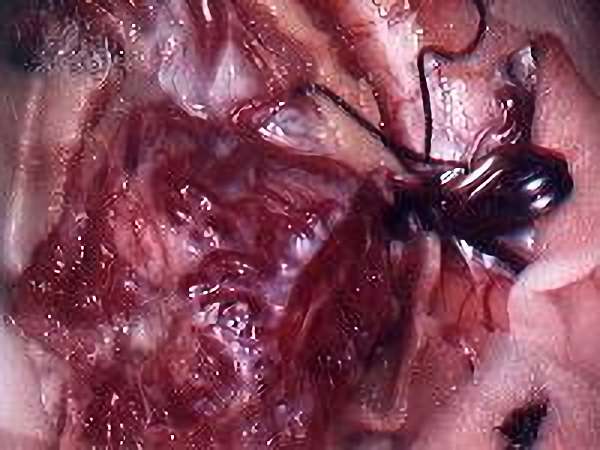

脳血管撮影

手術前

手術写真

手術中

手術後